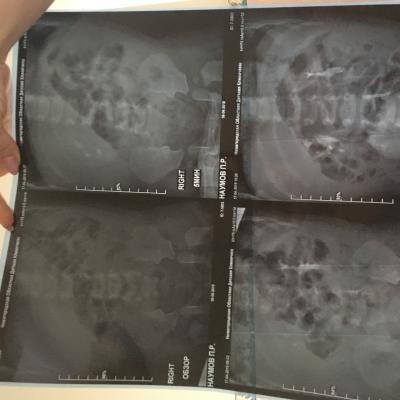

Здравствуйте , с Рождения поставлен диагноз уретерогидронефроз , пмр4 ст. Пол года назад сделали операцию по Коэну, но улучшений нет , рефлюкс стал 3 ст, а функция почки снижена . Лечащий хирург сказал, что ничего предпринимать не нужно, только наблюдение и высокая вероятность сморщивание почки и в последствии ее удаление. Скажите пожалуйста действительно ли уже не спасти почку ?!

Прилагаю снимки до операции и после операции.